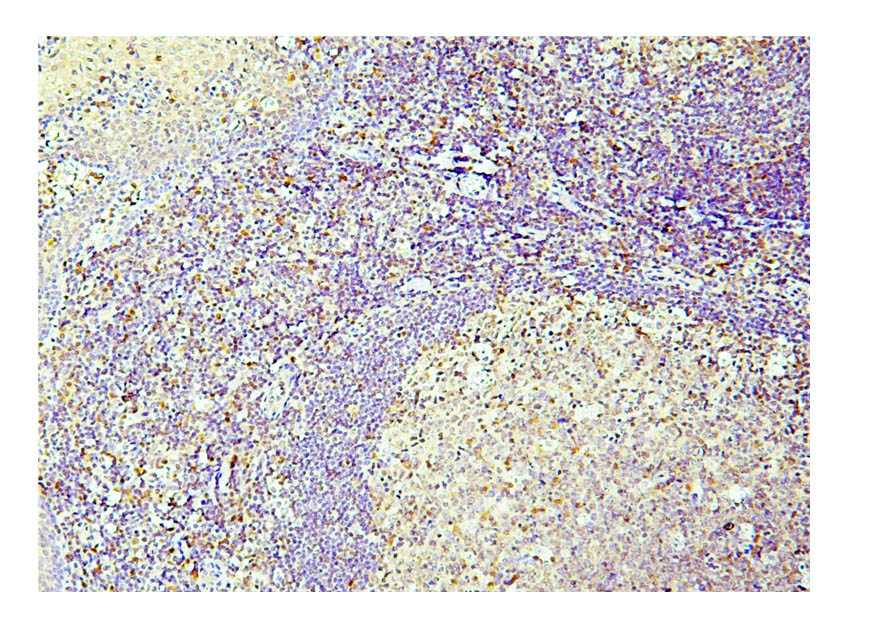

IHC analysis of Caspase 3/CASP3 (p17) using anti-Caspase 3/CASP3 (p17) antibody (M00334-6).

Caspase 3/CASP3 (p17) was detected in a paraffin-embedded section of human tonsil cancer tissue. Biotinylated goat anti-mouse IgG was used as secondary antibody. The tissue section was incubated with mouse anti-Caspase 3/CASP3 (p17) Antibody (M00334-6) at a dilution of 1:200 and developed using Strepavidin-Biotin-Complex (SABC) (Catalog # SA1021) with DAB (Catalog # AR1027) as the chromogen.